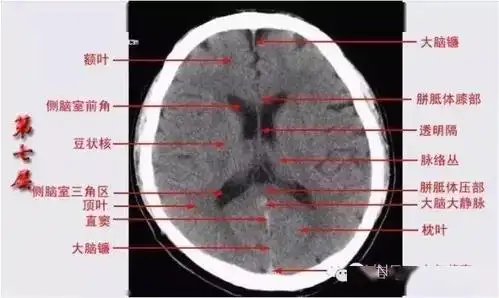

头颅ct解剖与常见出血梗死判读